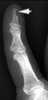

Subungual keratoma

Lucent defect in bones of hands, wrists, feet, or ankles